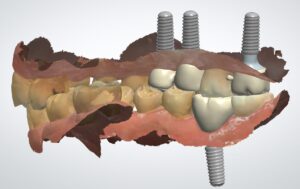

회복기간이 끝난 후에는 최종 보철물 제작을 위한 과정이 시작되었습니다.

최근엔 기존의 불편한 인상재료 대신 디지털 구강스캐너를 이용하여 환자분의 구강 내부를 정밀하게 스캔할 수 있습니다.

이 방법은 기존 방식에 비해 이물감이 현저히 적어 대다수 분들이 생각보다 전혀 불편하지 않다며 만족해하십니다.

또한 3D 프로그램을 통해 환자분의 구강구조와 기존 치아들과의 조화를 고려한 최적의 보철물 디자인이 가능합니다.

이러한 디지털 기술을 활용함으로써 더욱 정확하고 심미적으로도 우수한 결과를 얻을 수 있습니다.

드디어 최종 보철물을 보철물 장착한 후에는 치아가 다시 생기는 것이기 때문에 무엇보다 식사가 많이 수월해지게됩니다.